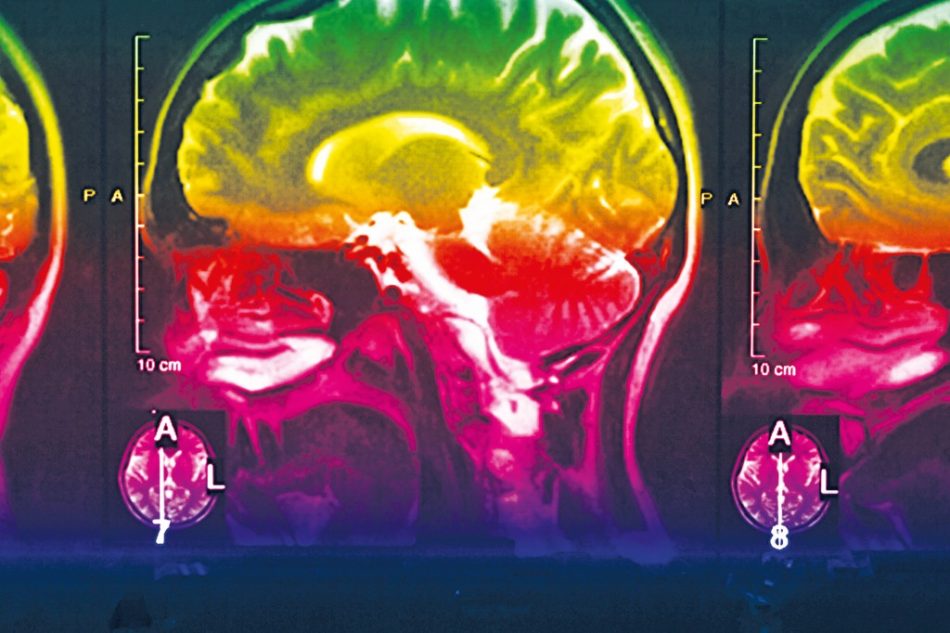

Big-Data-Analysen radiologischer Aufnahmen ebenso wie KI-unterstützte Beurteilungen von Schriftproben unterstützen die Früherkennung. Und letztlich fährt die Wissenschaft auf der Suche nach einem Medikament das komplette Repertoire an chemischer und biotechnologischer Forschung auf. Mit aktuellen Teilerfolgen. Immerhin soll ein Antikörperpräparat von Pharmakonzern Biogen in den USA vor der Zulassung stehen, verkündete die Alzheimer‘s Disease International, die Vereinigung aller Alzheimer-Verbände weltweit.